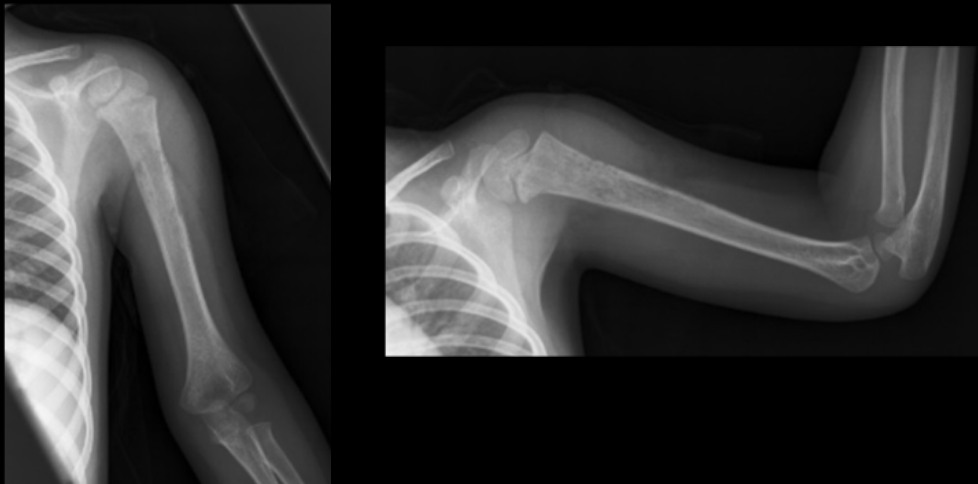

3

Q

What are the present soft tissue findings?

A

• Soft tissue emphysema

• Sequestrum

• Swelling

osteomyelitis

6

3-year-old male presents with leg pain and swelling. He is radiographed several days into his symptoms.

What radiographic infectious terms are present?

• Involucrum

• Cloaca

permeative lytic destruction (aggressive)